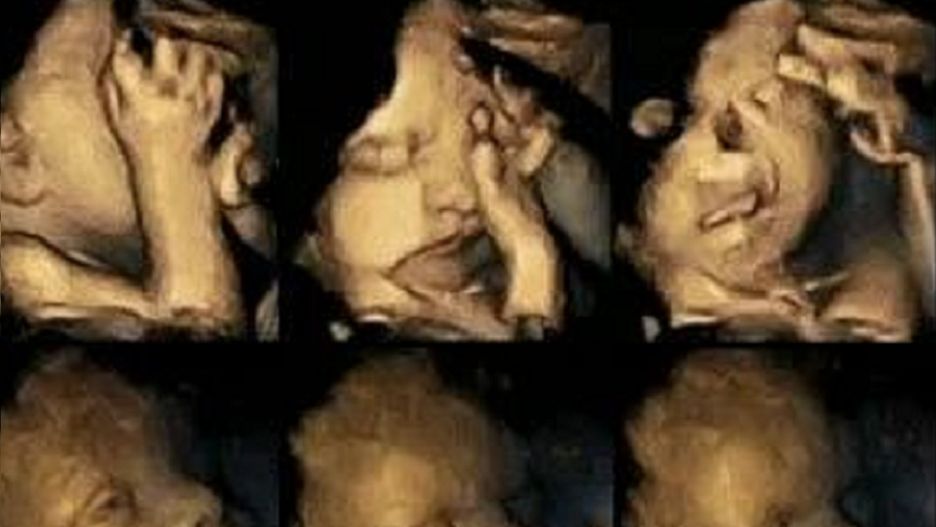

Wzory min płodu różnią się znacznie między płodami matek, które paliły, a płodami matek, które nie paliły. Wyniki te wskazują na fakt, że ekspozycja na nikotynę sama w sobie ma wpływ na rozwój płodu, poza takimi skutkami jak dodatkowy stres czy depresja - powiedziała Reissland, dodając, że potrzebne są pogłębione badania w tej dziedzinie.

Na górze pokazany jest płód matki palącej a niżej matki niepalącej.

Na górze pokazany jest płód matki palącej a niżej matki niepalącej. © Unveristy of Durham